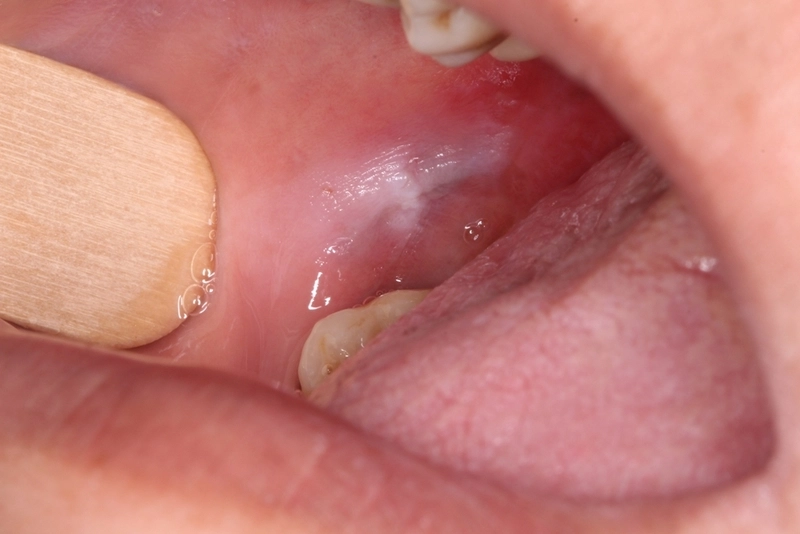

O câncer de boca, também conhecido como câncer de cavidade oral, é um tipo de neoplasia maligna que pode afetar os lábios, a língua, o assoalho da boca, o palato duro, as gengivas e outras regiões da cavidade oral. Segundo o Instituto Nacional do Câncer (Inca), essa doença é mais comum em homens e afeta 3,6 pessoas a cada 100 mil habitantes no Brasil.

Os principais tipos de câncer de boca diferem de acordo com a célula que deu origem ao tumor. O principal deles é o carcinoma de células escamosas (ou epidermoide), que corresponde a cerca de 90% dos casos e afeta principalmente as células que revestem a superfície da boca e da garganta. Porém, conforme se desenvolve, esse tumor pode se tornar invasivo e atingir tecidos adjacentes, incluindo os vasos e nervos, de tal forma que o tratamento do câncer de boca visa impedir o crescimento e suas complicações.

Durante a consulta, o médico fará uma anamnese detalhada e um exame físico para procurar lesões, nódulos ou áreas de descoloração na cavidade oral. Se alguma anormalidade for encontrada, exames adicionais podem ser solicitados, como biópsia, exames de imagem e, em alguns casos, a biópsia pode ser feita no consultório no mesmo dia, agilizando o diagnóstico do câncer de boca.